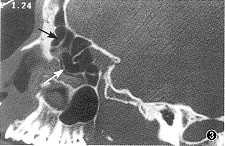

鼻丘气房位置分高、中、低3种,其2侧对称或不对称(图2)。高位鼻丘组双侧者10例,单侧为42例,共62侧(31%);中位鼻丘组双侧为24例,单侧为16例,合计64侧(32%);低位鼻丘组双侧为25例,单侧为24例,合计74侧(37%)。3种位置的出现率差异无显著性(P>0.05)。比较高位鼻丘气房与额窦发育的关系,额窦发育良好、中等和不良3组的例数分别为55、26、19例,3组中高位鼻丘分别为46、12、4侧,其出现率分别为41.8%、23.1%、10.5%,高位鼻丘的出现率与额窦发育呈正相关。此外,矢状位CT显示鼻丘位于筛泡的前上方,发育良好者可进入额窦(图3)。

图3 矢状位CT。可见气化良好的鼻丘(

)顶壁进入额窦,鼻丘们于筛泡(

)的前上方